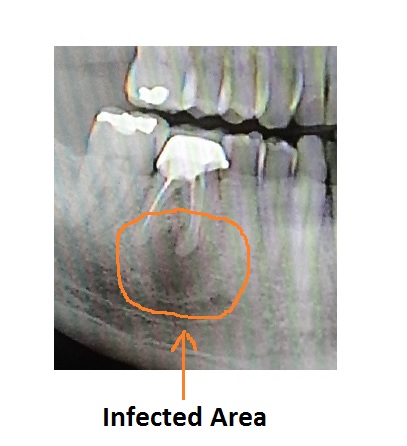

I had a root canal done on the lower, right side, first molar (Tooth #30) several years ago. This past November that same tooth got very painfully infected. My dentist prescribed an antibiotic and recommended that I have the tooth pulled and maybe get an implant or bridge. The Transplant Team concurred that I needed it pulled, but recommended against the implant or bridge. They always look towards the path of least infection potential.

They technology they have today is pretty impressive. The X-Ray machine at the orthodontist was like a small CT scanner and took a great image of my teeth and jaws in one shot.